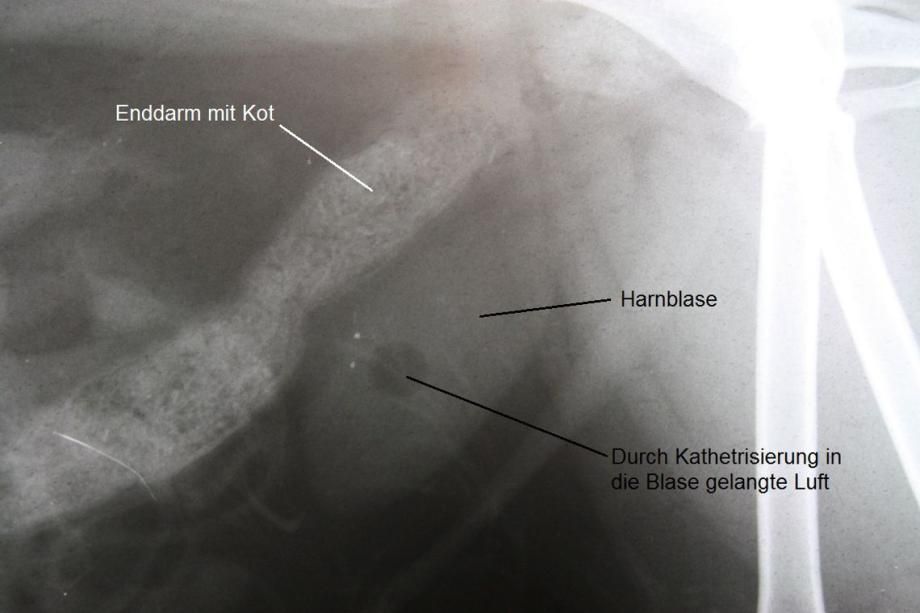

Unter Ultraschallkontrolle wird steriler Urin direkt aus der Blase entnommen und in einem externen Labor bakteriologisch untersucht - es werden aber keine Erreger festgestellt. Hingegen zeigt sich im Ultraschall, dass die Blase Fremdkörper enthält, welche einen Schallschatten werfen. Im Röntgen bestätigt sich die Vermutung, dass die Blase der Katze eine grosse Zahl sehr kleiner Steine enthält, welche röntgendicht ("weiss") erscheinen.

Da Ronja ein weibliches Tier ist, kommt hier eine elegante Methode zur Blasensteinentfernung zur Anwendung: Die Urohydro-Propulsion. Hierbei wird die Blase der Katze unter Narkose mit einem feinen Katheter mit Kochsalzlösung gefüllt. Das Tier wird anschliessend von einer Hilfsperson unter den Vorderbeinen so angehoben, dass die Katze aufrecht in der Luft hängt. Dadurch sammeln sich die Blasensteine im tiefstliegenden Punkt der Blase (dem Blasenhals) und können durch manuelles Auspressen der Blase mitsamt der Kochsalzlösung in die Harnröhre und damit ans Tageslicht befördert werden. Dieser Vorgang wird einige Male wiederholt, bis keine Blasensteine mehr ausgespült werden können. Ein abschliessendes Röntgen bestätigt die komplette Entfernung der mehreren Dutzend Blasensteine.